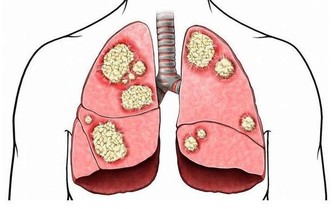

肺是人體極其重要的呼吸器官,是體內氧氣循環的關鍵。不過,現代很多人存在不良的生活和飲食習慣,比方說,時不時抽煙喝酒,動不動就熬夜……導致肺部功能或多或少受損,影響身體健康。那麼,肺好不好,可以通過哪些方法判斷?冬季養肺應該怎麼做?

④ 少吸煙

香煙對肺部的危害是很大的,是誘發肺癌的重要因素之一。因此,肺不好的人一定要盡量減少吸煙次數。